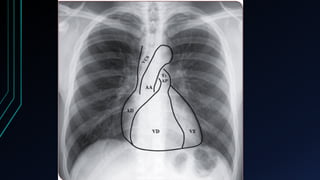

Projeção do Coração no Tórax

• Focos apicais

• Foco mitral -> 5º EIC esquerdo, linha hemiclavicular

• Foco tricúspide -> Base do apêndice xifoide, ligeiramente à esquerda

• Focos da base

• Foco aórtico -> 2º EIC direito, junto ao esterno

• Foco aórtico acessório -> 3º EIC esquerdo, próximo ao esterno

• Foco pulmonar -> 2º EIC esquerdo, junto ao esterno

*Observar outras localizações, como dorso, axila e pescoço (irradiações)